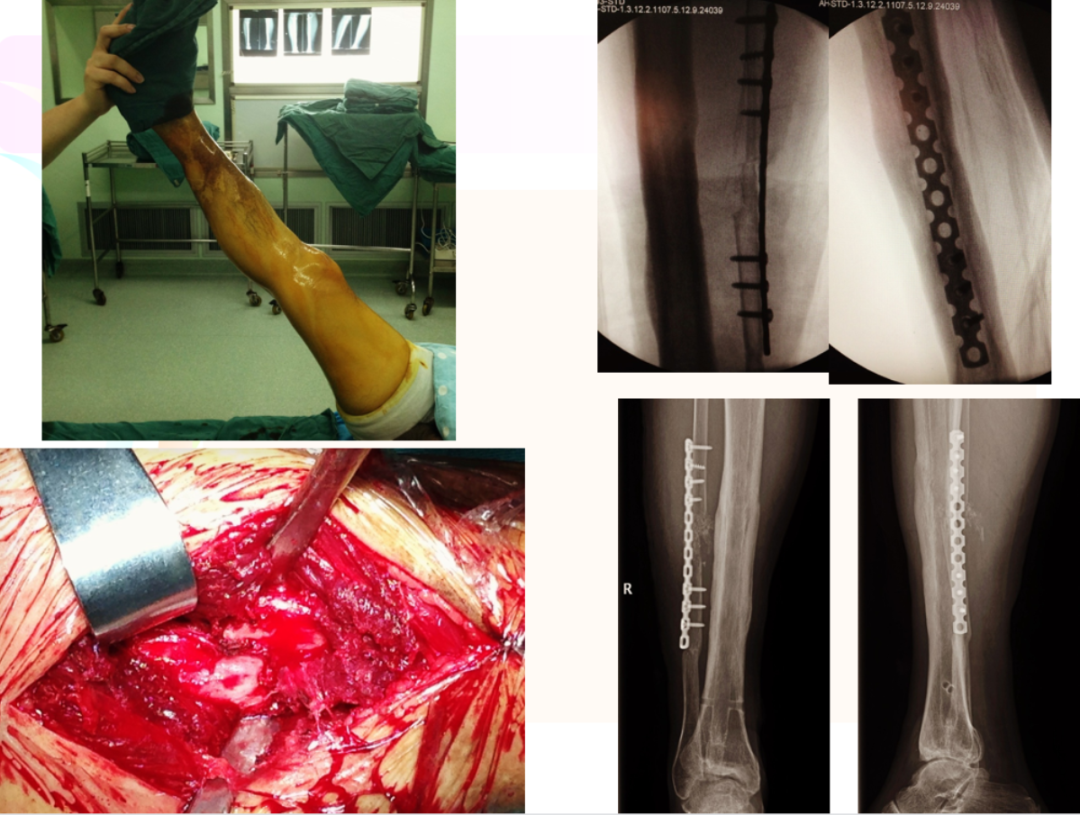

男性 车祸伤 42岁病例特点:高能量损伤;开放性骨折治疗:内固定选择?腓骨固定?